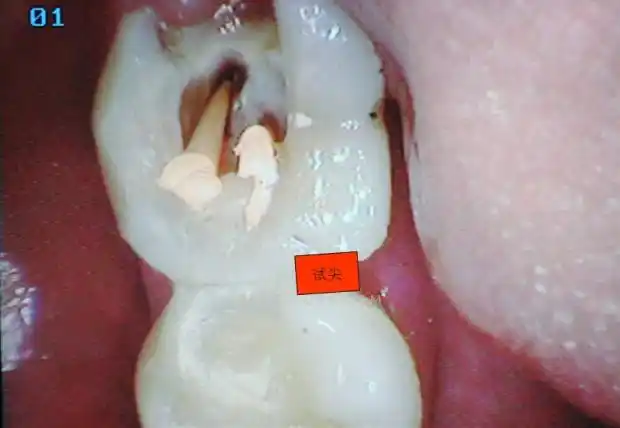

【经典病例】下7根管治疗到修复

在开始根管治疗前拍x线片,以帮助诊断,了解髓室的位置和根管数目,形态

下颌磨牙的根管预备规律分析多图病例总结